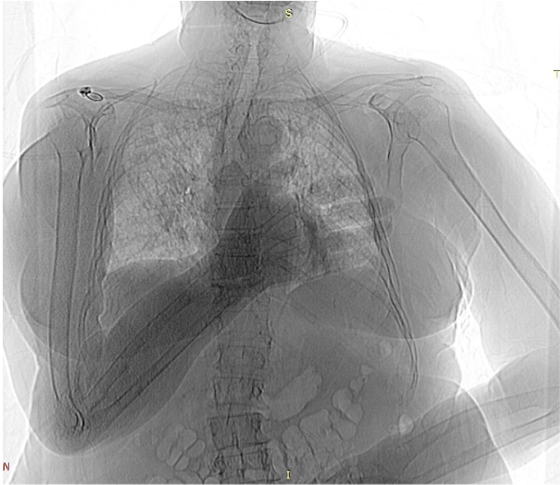

Этот цикл я писал, всматриваясь в медицинские снимки умирающего родного тела. Я пытался разглядеть его изнутри и осознать неосознаваемое: как это — постепенно умирать? Как отпустить, чем отстоять и куда его уложить, чтобы не было больно? В ужасе я наблюдал за расплывающимися узорами смерти, пока она не залила все живые уголки дряхлого тела. Снимки и тексты — свидетельства скрытого, немого страдания, которому я даю право быть увиденным и услышанным.

Это — кадиш по моей бабушке, которая умерла 18 января 2019 года. Была пятница, и похоронить ее нужно было до захода солнца — до начала Шаббата, который наступает в пятничный вечер. Кладбище было напротив больницы, через дорогу. Мы хоронили ее через три часа после смерти, не успев позвать ни родных, ни близких. Кадиш — это иудейская поминальная молитва. Для ее чтения необходим миньян — десять мужчин. Нас было меньше, поэтому хоронили без молитвы, спешно. Эти стихотворения — мой кадиш, который тогда мне произнести не дали, мое отпевание пустоты, что осталась после нее. В кадише использованы реальные медицинские материалы — рентгеновские снимки, УЗИ, КТ, ЭКГ — из истории болезни бабушки, с момента обнаружения рака и до самой смерти. Последняя кардиограмма была снята с мертвого тела. Так требовал больничный протокол.